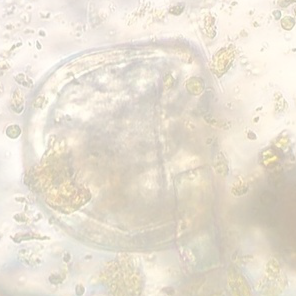

Größe/Aussehen: männlich circa 0,8 – 1,5 cm, weiblich: 2,5 – 12 cm; weißliche, teils durchsichtige filigrane Würmer mit meist durchsichtigem, spitz zulaufendem Schwanz – ähneln einer Sojasprosse Achtung: Gerne werden Oxyuren mit Spulwürmern verwechselt!

Nachweis: In der Kotprobe ein reiner Zufallsbefund, von daher gilt hier die Sichtung der Würmer am After, oder im Kothaufen, sowie die Sichtung der Eiablage am After als „beweisend“. Ebenfalls kann ein Tesaabklatsch zur Untersuchung eingesandt werden oder ein Bild des Fundes.